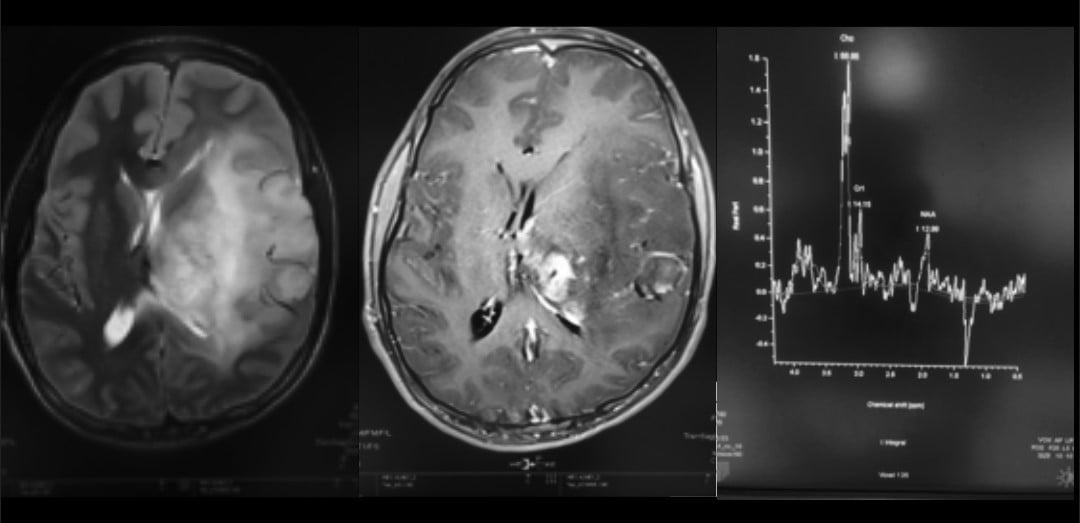

| T2-Weighted Imaging | Hypointense (caseating granulomas) or hyperintense (non-caseating granulomas); surrounded by edema | Hyperintense with surrounding vasogenic edema; heterogeneous in higher grades |

| FLAIR Imaging | Partial suppression in caseating granulomas with liquefaction | Hyperintense signal; useful for delineating tumor margins and edema |

| Contrast Enhancement | Rim enhancement (caseating granulomas) or homogeneous enhancement (non-caseating granulomas) | Ring or nodular enhancement in high-grade gliomas; low-grade gliomas may lack enhancement |

| MR Spectroscopy | Elevated lipid-lactate peaks, reduced N-acetylaspartate (NAA)/creatine (Cr) ratio | Elevated choline (Cho), reduced NAA, and increased Cho/NAA ratio due to tumor metabolism |